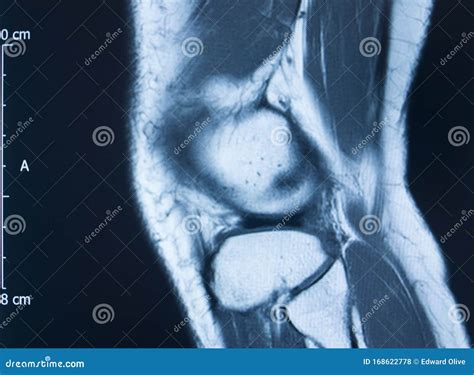

An Mcl Tear Mri is a non-invasive imaging technique that provides detailed images of the knee joint. MRI uses magnetic fields and radio waves to create cross-sectional images of the body’s internal structures. This allows healthcare professionals to visualize the MCL and other soft tissues in the knee, identifying any tears or damage.

During an *Mcl Tear Mri*, the patient lies on a table that slides into a large, cylindrical machine. The procedure is painless and typically takes about 30-60 minutes. The MRI machine captures multiple images from different angles, providing a comprehensive view of the knee joint.

An *Mcl Tear Mri* is particularly useful for differentiating between an MCL tear and other knee injuries, such as meniscal tears or anterior cruciate ligament (ACL) injuries. This information is crucial for developing an appropriate treatment plan.